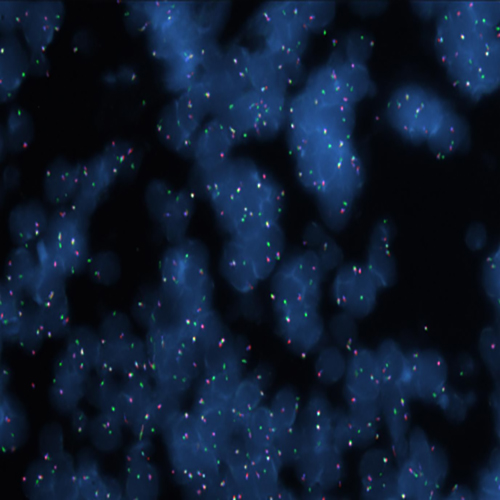

Hybridization of MYC TC break probe to a tissue section showing aberrant pattern (1GBR1G1BR).

RUO - MYC (8q24) Triple-Color, Break (tissue)

Rearrangements of the proto oncogene MYC c-myc) have been consistently found in Burkitt's lymphoma tumor cells. In cases with the common t(8;14) chromosomal translocation, the MYC gene is translocated to chromosome 14 and rearranged with the immunoglobulin heavy chain genes; the breakpoint occurs 5' to the MYC gene and may disrupt the gene itself. In Burkitt's lymphoma showing the variant t(2;8) or t(8;22) translocations, the genes coding for the k and l immunoglobulin light chain are translocated to v-myc avian myelocytomatosis viral oncogene homolog (MYC or c-myc) chromosome 8. The MYC (8q24) Break probe is optimized to detect rearrangements involving the 8q24 locus in a triple-color, split assay on formalin fixed paraffin embedded tissue.